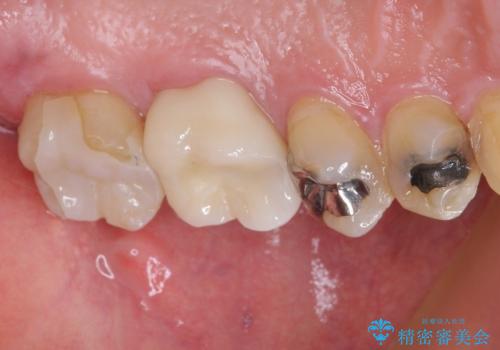

フロスの引っ掛かりもなくなり、食べ物もはさまりにくくなったそうで、満足されました。

定期的にメンテナンスで来院される患者様なのでレントゲン等で虫歯の進行を確認し、必要があれば隣在歯の治療に介入していく予定です。